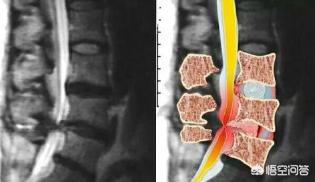

Die Pathogenese des lumbalen Bandscheibenvorfalls ist auf die Degeneration der lumbalen Bandscheibe (bestehend aus Nucleus pulposus, Annulus fibrosus und Knorpelplatte) zurückzuführen, wobei der Annulus fibrosus teilweise oder vollständig reißt und der Nucleus pulposus hervortritt, um die Nervenwurzel und die Cauda equina zu reizen oder zu komprimieren, was ein Syndrom und eine häufige degenerative Erkrankung der Wirbelsäule in der Klinik ist. Es handelt sich um ein Syndrom und eine häufige degenerative Erkrankung der Wirbelsäule, die sich vor allem durch Symptome wie Lendenschmerzen, Ischiasbeschwerden, Taubheitsgefühl in den unteren Gliedmaßen und Cauda-Equina-Syndrom äußert.

Es handelt sich um einen teilweisen Riss der inneren Schichten des Faserrings, während die äußeren Schichten intakt sind, wenn sich der Nucleus pulposus aufgrund von Druck in den Wirbelkanal vorwölbt, die Oberfläche jedoch glatt ist. Eine konservative Behandlung dieses Typs führt meist zur Remission oder Heilung.

Bandscheibenvorfall in der Lendenwirbelsäule

Der Faserring ist vollständig zerrissen und der Nucleus pulposus ragt in den Wirbelkanal, das hintere Längsband bleibt jedoch intakt. Die Notwendigkeit einer Operation richtet sich nach der Schwere der Erkrankung.

Bandscheibenvorfall

Der Nucleus pulposus durchbricht das hintere Längsband und gelangt in den Wirbelkanal, seine Wurzel bleibt jedoch im Zwischenwirbelraum. Die chirurgische Behandlung kann je nach Zustand entschieden werden.

freier lumbaler Bandscheibenvorfall

Das Pulposus-Gewebe bricht durch den fibrösen Annulus und das hintere organische Band und ragt vollständig in den Wirbelkanal, wobei es sich von der ursprünglichen Bandscheibe löst. Die chirurgische Behandlung kann je nach Zustand entschieden werden.

Bandscheibenvorfälle in der Lendenwirbelsäule verursachen Ischiasnervenschmerzen, die am häufigsten mit lumbalen 3-sakralen 1-Bandscheibenläsionen in Verbindung gebracht werden, die dadurch entstehen, dass der Bandscheibenvorfall Druck auf die Nervenwurzel ausübt.

Die Bandscheibe ist eine faserige Struktur, die zwei Wirbel miteinander verbindet. Sie besteht aus einem peripheren Faserring und einem wasserreichen Gallertkern in der Mitte. Degeneration der Bandscheibe, schlechte Körperhaltung, langes Sitzen und Stehen, Kälte und Nässe führen zu einer Schädigung des peripheren Faserrings der Bandscheibe, der Nucleus pulposus im Zentrum der Bandscheibe tritt hervor und drückt auf die Nervenwurzel. Klinische ErscheinungsformenLangfristig können Kreuzschmerzen, ausstrahlende Schmerzen und Taubheitsgefühle in den unteren Gliedmaßen sowie Muskelschwund in den unteren Gliedmaßen auftreten. Wenn der Nervus cauda equina durch die Vorwölbung komprimiert wird, äußert sich dies in einer Störung des zweiten Stuhlgangs und einem Taubheitsgefühl im Dammbereich.